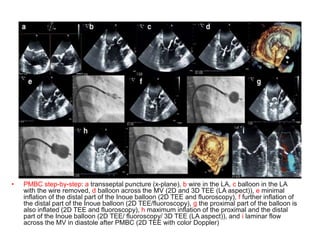

• PMBC step-by-step: a transseptal puncture (x-plane), b wire in the LA, c balloon in the LA

with the wire removed, d balloon across the MV (2D and 3D TEE (LA aspect)), e minimal

inflation of the distal part of the Inoue balloon (2D TEE and fluoroscopy), f further inflation of

the distal part of the Inoue balloon (2D TEE/fluoroscopy), g the proximal part of the balloon is

also inflated (2D TEE and fluoroscopy), h maximum inflation of the proximal and the distal

part of the Inoue balloon (2D TEE/ fluoroscopy/ 3D TEE (LA aspect)), and i laminar flow

across the MV in diastole after PMBC (2D TEE with color Doppler)

• PMBC step-by-step:a transseptal puncture (x-plane), b wire in the LA, c balloon in the LA with the wire removed, d balloon across the MV (2D and 3D TEE (LA aspect)), e minimal inflation of the distal part of the Inoue balloon (2D TEE and fluoroscopy), f further inflation of the distal part of the Inoue balloon (2D TEE/fluoroscopy), g the proximal part of the balloon is also inflated (2D TEE and fluoroscopy), h maximum inflation of the proximal and the distal part of the Inoue balloon (2D TEE/ fluoroscopy/ 3D TEE (LA aspect)), and i laminar flow across the MV in diastole after PMBC (2D TEE with color Doppler)